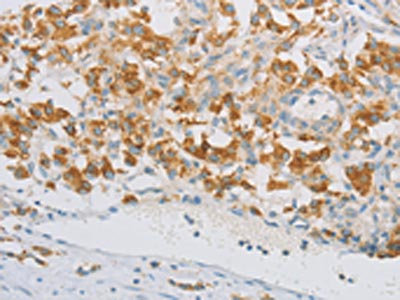

The image on the left is immunohistochemistry of paraffin-embedded Human cervical cancer tissue using CSB-PA284388(REN Antibody) at dilution 1/40, on the right is treated with fusion protein. (Original magnification: ×200)

The image on the left is immunohistochemistry of paraffin-embedded Human thyroid cancer tissue using CSB-PA284388(REN Antibody) at dilution 1/40, on the right is treated with fusion protein. (Original magnification: ×200)